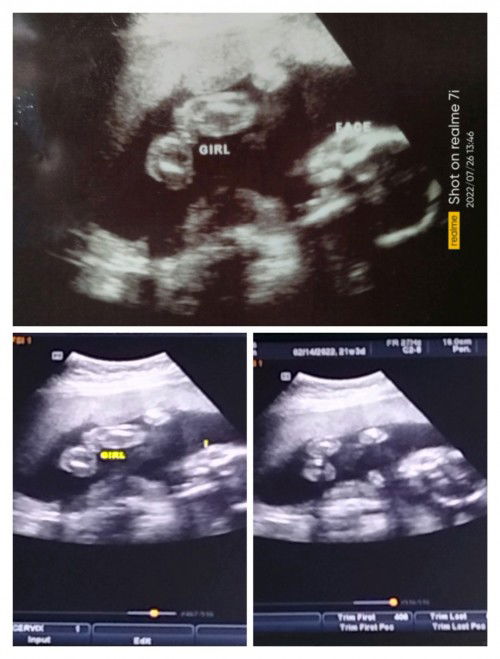

Hello po ☺️ 21 weeks pa lang po Ako nyan and kapag girl daw po usually mahirap daw po Makita ung gender nya . Pero Sabi po Nung nag ultrasound sakin and base sa result po girl daw po si baby ko . since 21 weeks pa lang po sya , sure na po Kaya yon? Kayo po mga mommies or sa marunong po tumingin Ng Ultrasound, girl po ba talga si baby ko? Salamat po#pregnancy #1stimemom #firstbaby